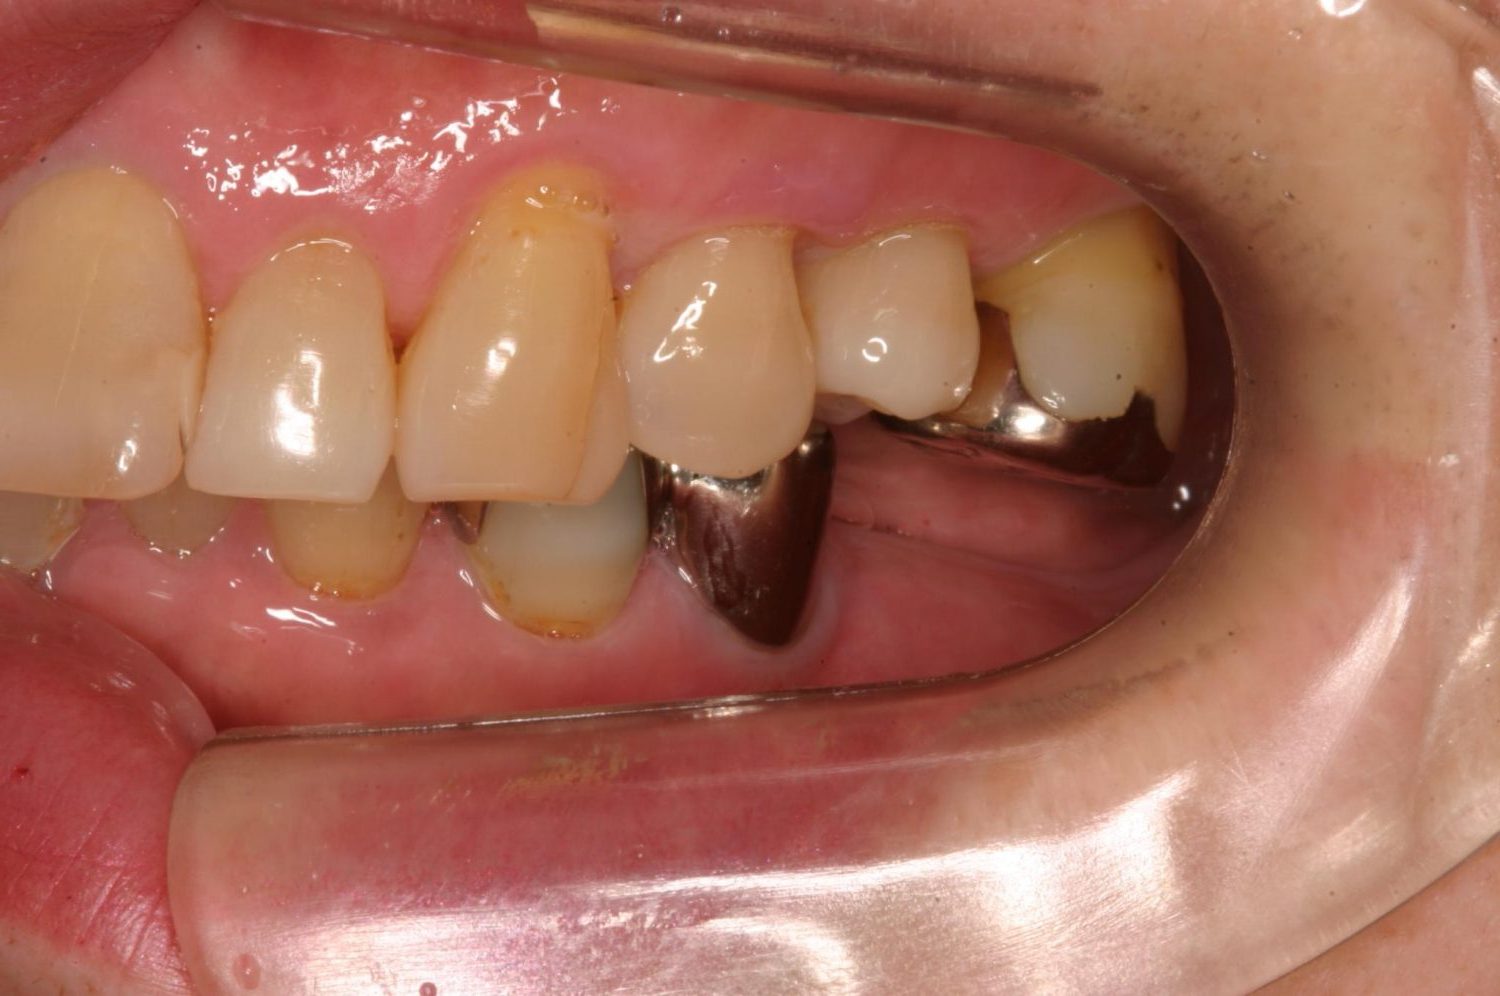

インプラント治療の症例紹介⑥

Before

After

主訴

咬めるようになりたい

治療内容

保存不可能な歯の抜歯、上下の咬み合わせを揃えて欠損部にインプラント治療

治療費

2,508,000円(税込)

治療期間

19ヶ月

通院回数

26回

想定されたリスク

※血糖値の高い方で、咬めるようになると高血糖となる可能性があるため食事制限が必要となる。インプラント周囲炎の恐れがありました。

歯の欠損による対合歯の挺出等を修正し咬合平面を揃えた症例